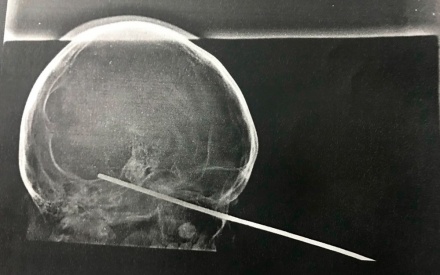

Menino de 8 anos tem espeto cravado no olho durante brincadeira com amigo na Bahia; raio-x mostra objeto

Um menino de 8 anos, identificado pelas iniciais R.S.S, teve um espeto de churrasco cravado no olho enquanto brincava com um amigo, na cidade de Santa Luzia, no sul da Bahia. Uma foto do raio-x da face da criança foi divulgada pelo hospital e mostra a posição do espeto na cabeça do garoto. [Veja imagem acima]

O caso aconteceu na tarde de domingo (22), mas as informações só foram divulgadas nesta segunda (23). A criança foi socorrida para o Hospital Calixto Midlej Filho, na cidade de Itabuna, que fica a cerca de 100 quilômetros de Santa Luzia. De acordo com a Santa Casa de Misericórdia de Itabuna, que administra a unidade, o objeto passou pelo seio cavernoso e ficou no tronco encefálico, que é uma cavidade oca entre os ossos localizada no cérebro. Na unidade, o menino passou por cirurgia e foi levado para o Centro de Tratamento e Terapia Intensiva do Hospital Manoel Novais, também administrado pela Santa Casa, no final da tarde. O estado de saúde dele é estável.